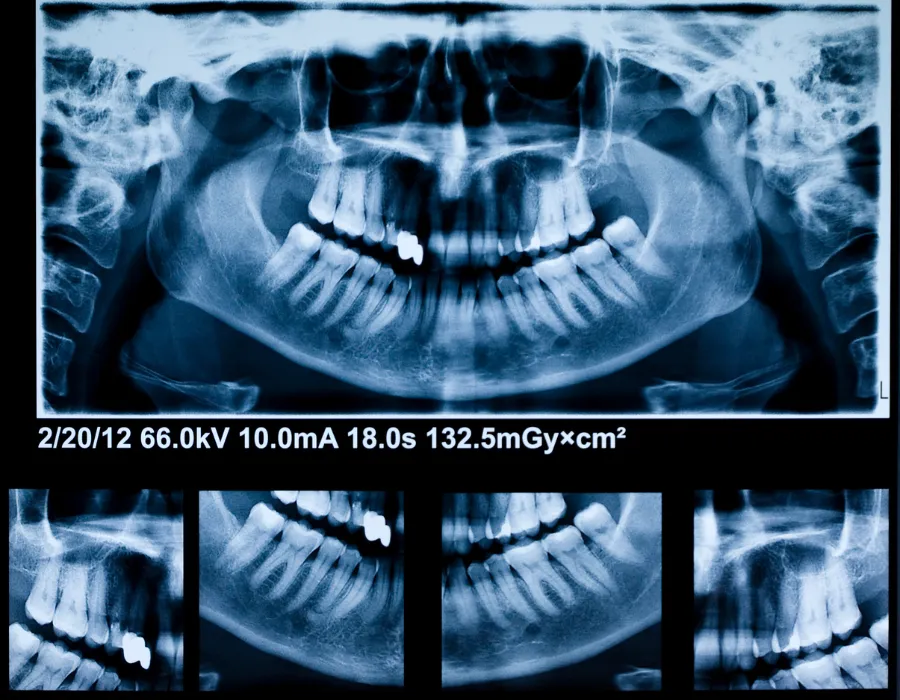

Dental X-Rays

About Dental X-Rays

At The Global Dentist, we provide advanced dental X-rays in Islamabad using modern, low-radiation digital technology. Our clinic in G-8 Markaz, Islamabad, offers safe and precise dental imaging to detect problems early and plan effective treatments. Patients searching for a dentist near me, a dental clinic near G-8 Markaz, or a trusted dentist in Islamabad choose us for our accurate diagnosis, patient comfort, and expert dental care.

Located at Chohan Plaza, G-8 Markaz, Islamabad, our clinic offers high-quality Dental X-Rays in a comfortable and welcoming environment.